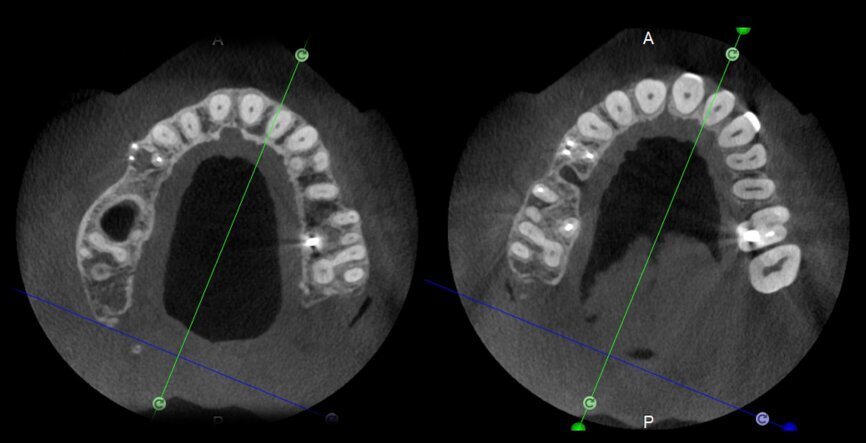

The case with which I would like to start my clinical review is a perfect example of how difficult it is to establish the origin of the patient’s symptoms on the basis of an intraoral radiograph alone. Not only does the 2D study fail to establish with certainty the presence of a lesion, but more importantly, it is impossible to establish the size, morphology and type of the lesion. An analysis of the 3D imaging, however, provides a clear picture of the clinical situation: the coronal and sagittal slices revealed the presence of a large lesion extending from the apex of the mesial root of this molar to the furcation, while the axial slices allow us to conduct a precise analysis of the endodontic anatomy and, in particular, the shape of the mesial root, which in this case was fused with the palatine root. A full overview of the case can, therefore, guide the decision-making process and direct the treatment plan towards a specific type of treatment (Figs. 1–4).